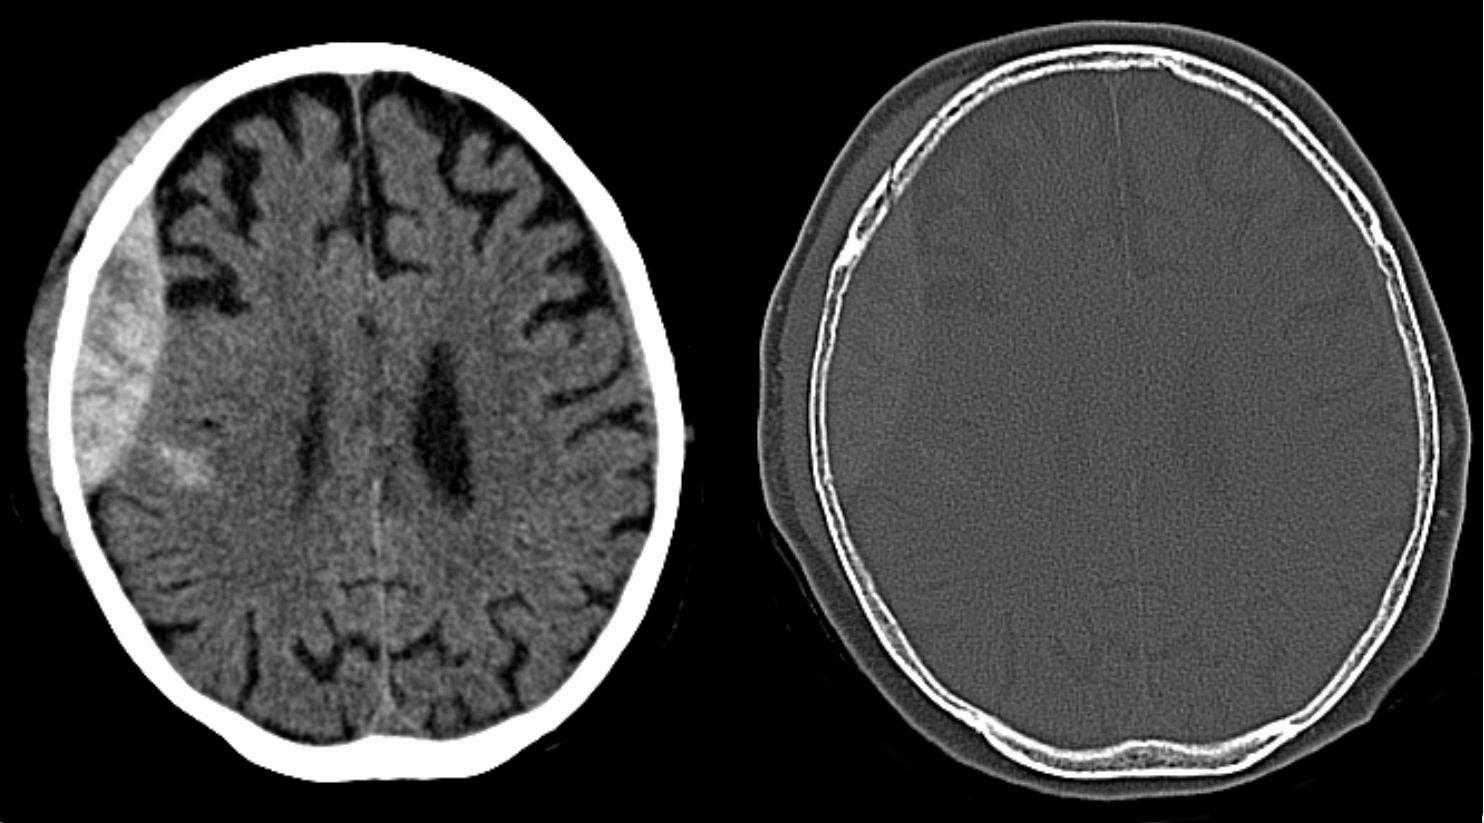

硬腦膜上出血

硬腦膜是腦膜最外層,硬腦膜上出血即腦膜與頭骨之間出血。患者或有「清醒期」,即腦部有出血但人仍清醒、舉止正常,但持續出血並壓迫到腦部組織,就可能突然失去意識。如出血量大,須手術移除血塊。